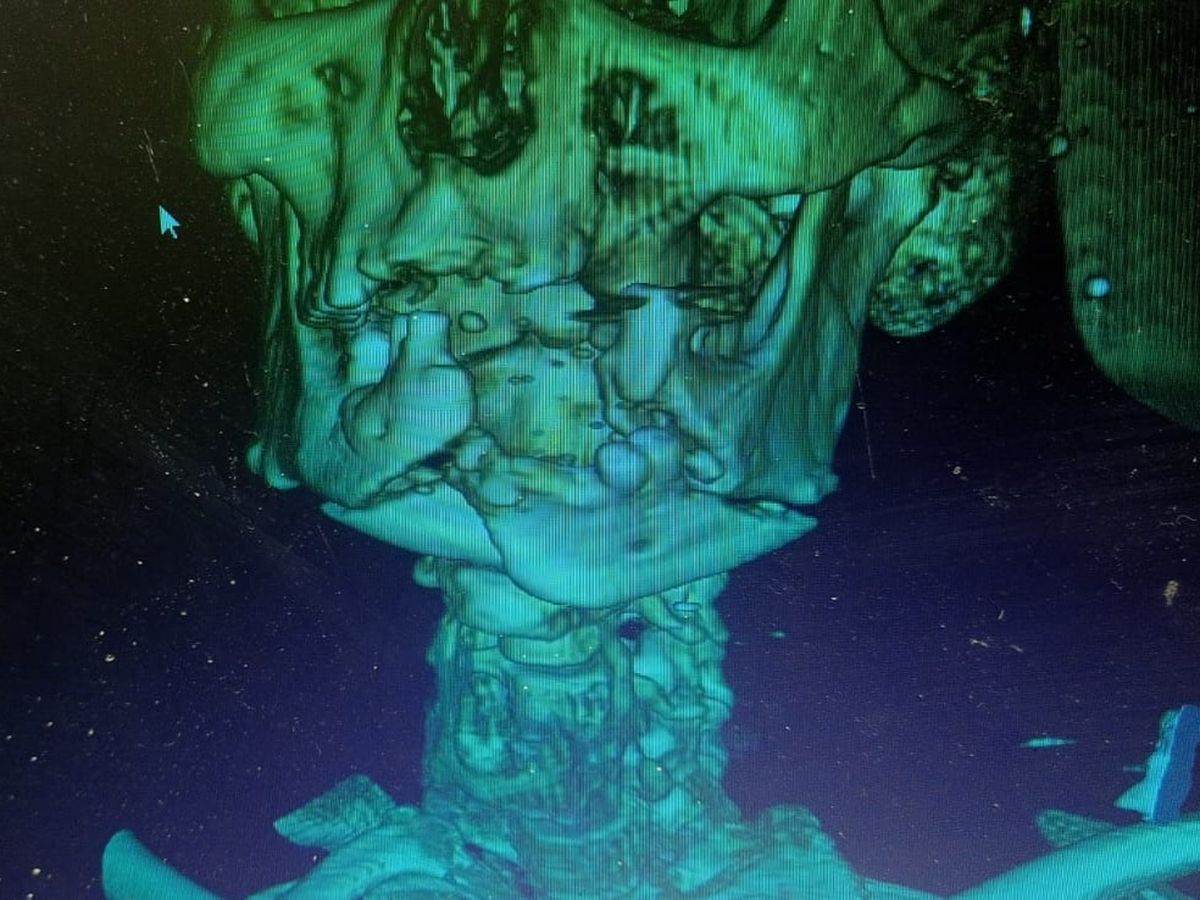

Our father was severely injured while attempting to secure an aid parcel from the GHF site! He suffered a bullet which fractured his jaw terribly. He is in a state of constant pain and requires complex surgeries to fully repair the damage. The doctors here did as much as they could for him, but he needs further treatment abroad. The medication required and the follow up monitoring are very expensive here. So we have amended this campaign to include the urgent need for his treatment on top of our basic survival needs. Please read below for the story of our journey over two years and give what you can. Thank you from the bottom of our hearts for your support.